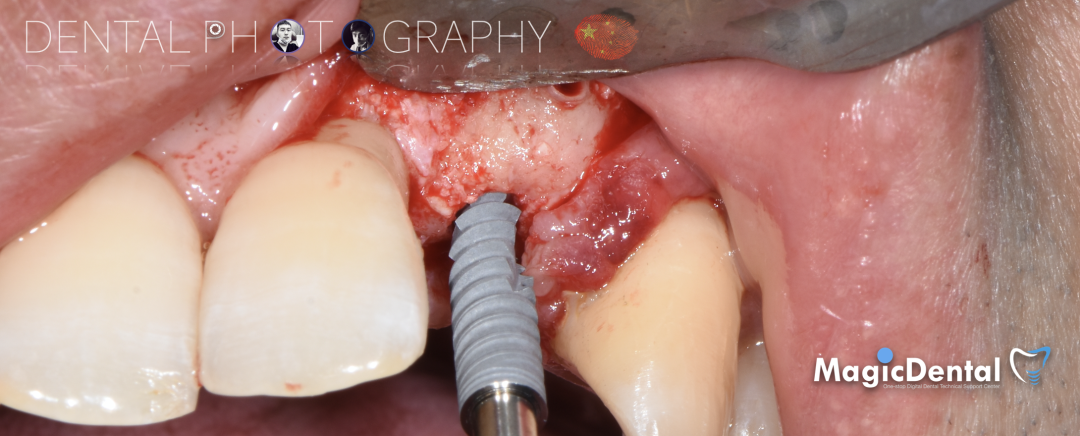

切开翻瓣,彻底暴露术区,试戴骨块。

调整骨块外形,适配受植区域,打开骨髓腔。

预备固位钉洞,固定骨块

骨膜减张,放置骨粉,放置骨块,钛钉固定骨块。